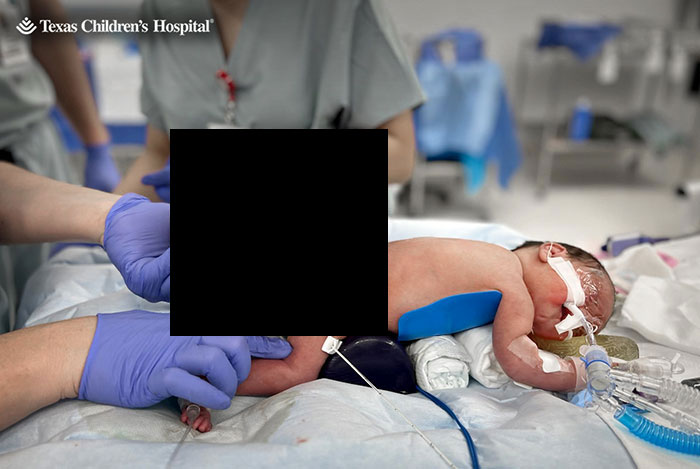

On May 21, at 34 weeks, Kristin delivered Adalida via C-section. The little baby girl was born with the dreaded four-pound tumor, nearly two-thirds of her body weight.

Combined, the baby and tumor weighed more than 10 pounds (approximately 4.5 kilograms). Dr. Nassr recalled the tumor size being “a little bit smaller than a watermelon,” but larger than a cantaloupe.

He told People: “It was a big tumor, that’s why we were so worried. “We needed to be very careful during delivery.

“We had to avoid any trauma or rupture of the tumor. Because sometimes with that large of a tumor, it can rupture and can start bleeding, and baby can become very sick after delivery.”

Kristin, who had only been able to see Adalida for a “split second” through a TV camera, recalled the moment her daughter was immediately taken to the neonatal intensive care unit: “I had just had her, and I was crying and I was upset.”

Two days later, a pediatric surgery team was able to remove the tumor successfully, and Adalida went home from the hospital on her due date, June 29, People reported.